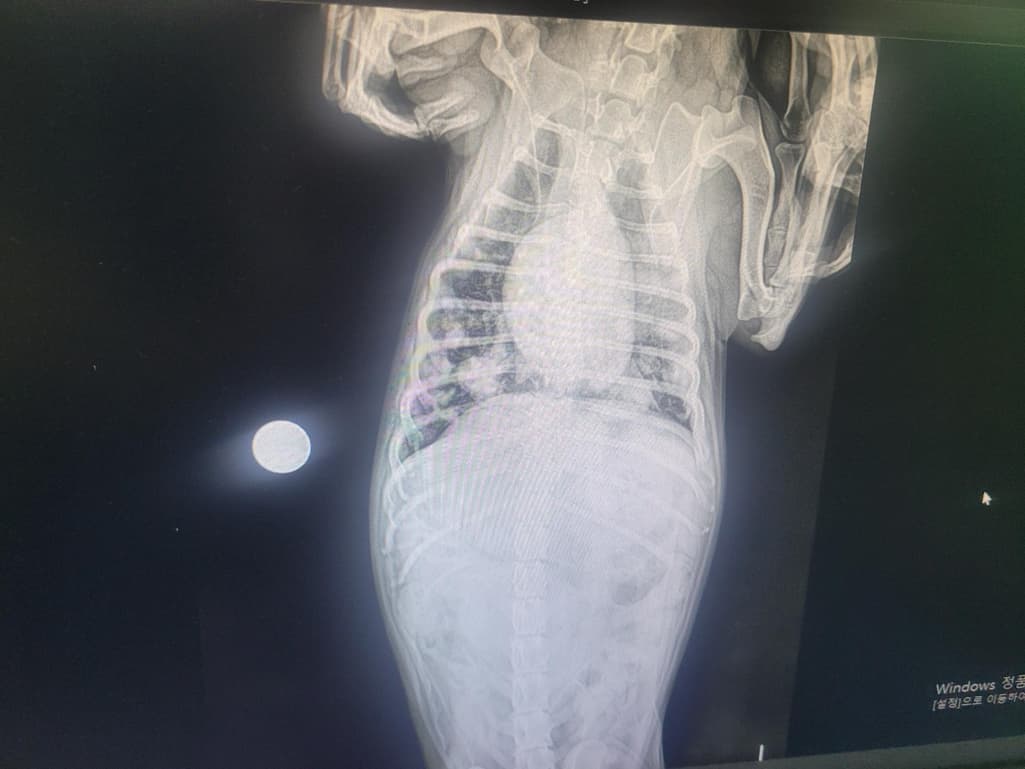

보호자님께서 올려주신 영상을 확인했을 때, 의심되는 정황은 있습니다. 다만 엑스레이의 화질이 떨어져 정확한 판단이 어려운 점 감안해주시기 바라며, 정확한 판단은 항상 병원에 내원하셔서 수의사를 통해 이루어져야 합니다.

흉부 방사선상 종양 전이 의심 상황

폐야에서 다발성으로 둥글고 경계가 비교적 뚜렷한 결절들이 보이는데, 이는 전형적으로 전이성 종양에서 흔히 관찰되는 형태입니다 (다른 장기에서 폐로 전이). 하지만, 드물게는 감염성 병변에서도 비슷한 양상이 보일 수 있어 확정적이지는 않습니다.간비대

복부 영상에서 간이 정상보다 커져 있는 모습이 의심됩니다. 간비대는 종양, 대사성 질환 등 다양한 원인에서 나타날 수 있습니다. 따라서 간비대 자체는 반드시 종양과만 연결되는 소견은 아니며, 추가적인 혈액검사와 초음파 정밀 평가가 필요합니다.

핵심적으로, 현재 영상 소견만으로는 종양성 질환 가능성이 높지만, 현재 엑스레이 사진으로는 폐로 종양이 전이되었을 가능성을 시사할 뿐, 추가적인 검사를 통한 확인이 필요합니다. 확정하려면 정밀검사가 필요하다는 점을 말씀드립니다.만 정확한 확인을 위해서는 혈액검사, CT 촬영 등이 필요할 것으로 보입니다. 다만 소형견으로 보이는 형태에, 체중이 2kg가 빠졌다면 만성 질환의 가능성이 크므로 빠른 시일 안에 정밀 검사를 추천드립니다.

사진 화질이 너무 나빠서 정확한 평가는 할 수 없으나 확실한것은 전이성 폐종양 가능성이 매우 높으니 CT 검사를 포함한 정확한 영상 검사를 추가로 받으시기 바랍니다. 보호자가 주춤하다가 환자를 빨리 죽이게 됩니다. 주춤하지 마시길,